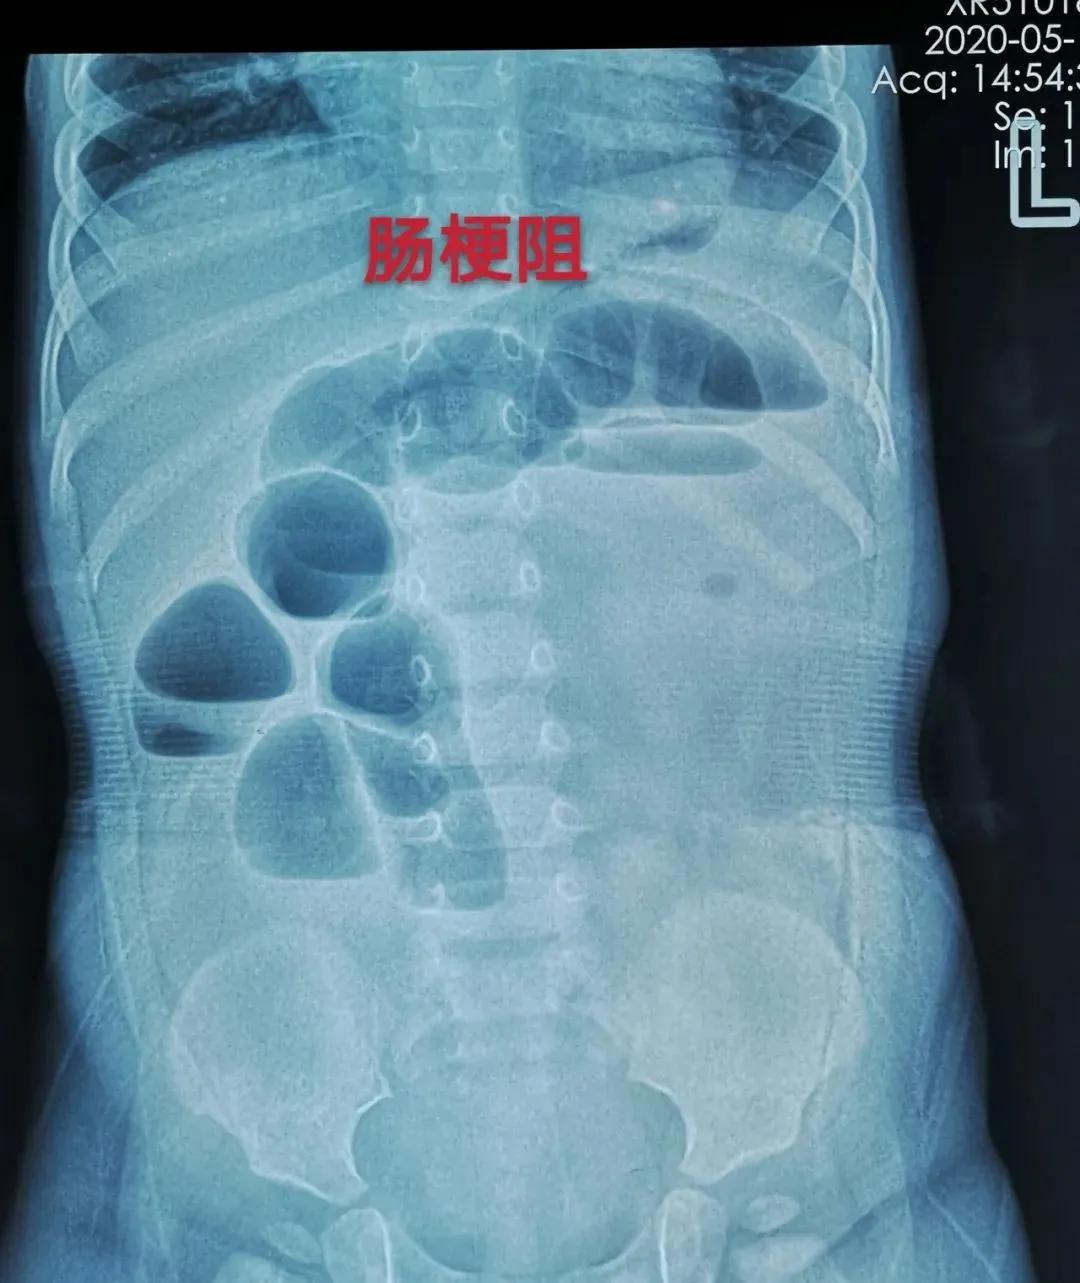

原来,1岁多的佳佳(化名)在就诊前几天,出现了精神差、哭闹、拒食、频繁恶心呕吐、腹胀、不排大便的情况,佳佳母亲带着他到当地医院就诊,可当地数家医院虽然考虑佳佳为肠梗阻,但却查不出梗阻的原因。

凭借多年从医经验,谷雅川立即做出诊断:孩子的肠梗阻是由消化道异物引起的。随即联系超声科医生杨坡对佳佳进行超声检查后,确认消化道异物是“海绵宝宝”。

医护团队为佳佳采取了腹腔镜手术。术中证实,消化道异物就是回肠末段异物——直径逾3厘米的“海绵宝宝”。